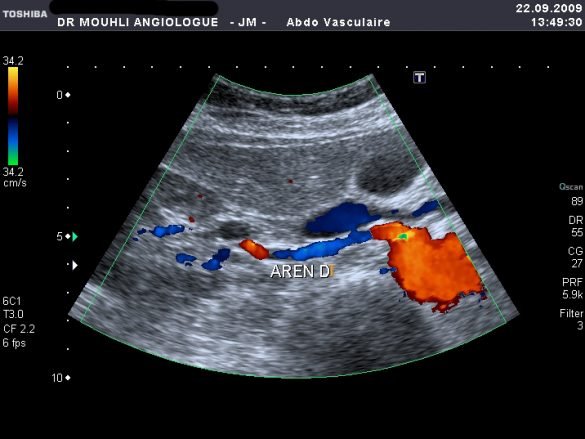

L’ÉCHO-DOPPLER

L’écho-doppler rénal est un moyen non invasif et peu coûteux d’apprécier le retentissement hémodynamique d’une sténose d’une artère rénale (fig. 1, voir page suivante). Une stratégie de dépistage basée sur l’écho-doppler permet de diminuer le nombre d’angiographies diagnostiques et d’augmenter le nombre potentiel de patients avec une hypertension rénovasculaire qui sont susceptibles de bénéficier d’un traitement par angioplastie ou chirurgie. Les performances de l’écho-doppler ont été améliorées grâce aux innovations technologiques comme le doppler couleur, le doppler énergie, et l’imagerie harmonique (tableau 1).11-15 L’introduction des produits de contraste échographiques a permis de diminuer le temps d’examen et d’améliorer la fiabilité diagnostique en augmentant le signal doppler artériel.16 Certains travaux récents ont montré que l’administration d’un inhibiteur de l’enzyme de conversion (captopril) peut majorer les signes indirects de sténose et offre donc des perspectives dans l’évaluation fonctionnelle de la SAR et la démonstration d’un lien causal avec diagnostic de l’HTA.17 L’écho-doppler reste un examen très dépendant de l’opérateur et nécessi-te un plateau technique de haute gamme. Une connaissance parfaite des variantes anatomiques, des signes et des seuils pathologiques traduisant une sténose significative est primordiale (tableau 2). Le taux d’échecs s’élève cependant à environ 10-20%, ceci même pour un opérateur très expérimenté (morphotype du patient, surprojections aérodigestives, et absence de coopération du patient).14